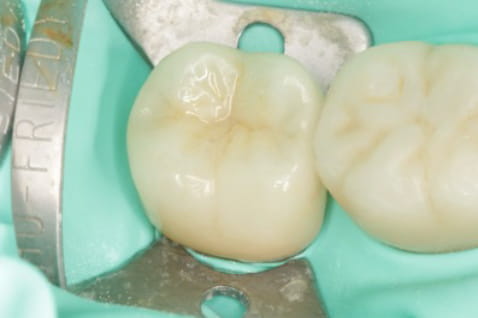

根管の中を封鎖し、根管治療終了

根管治療が終わったところが、また隙間から感染しないように、

上から被せを精密に接着させ、密封。